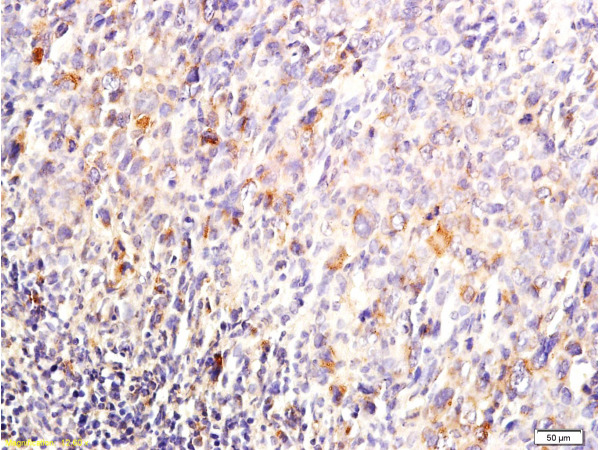

Paraformaldehyde-fixed, paraffin embedded Mouse colon; Antigen retrieval by boiling in sodium citrate buffer (pH6.0) for 15min; Block endogenous peroxidase by 3% hydrogen peroxide for 20 minutes; Blocking buffer (normal goat serum) at 37°C for 30min; Antibody incubation with DUSP1/MKP1 Polyclonal Antibody, Unconjugated (bs-1851R) at 1:400 overnight at 4°C, DAB staining.